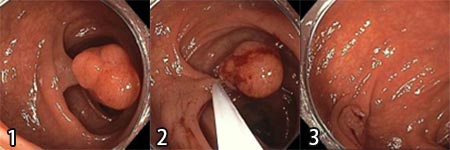

ホットポリペクトミー(Hot Polypectomy)

主に茎のあるタイプのポリープが対象です。

こちらは使用する鉗子に高周波電流を流し、焼灼することで止血を行います。

茎部分には太めの血管が通っているため、止血を十分に図り、切除する必要があるからです。

- ポリープの茎に鉗子をかけます(写真は12mm大のポリープ)。

- 鉗子のワイヤーを締め上げると同時に通電してポリープの茎の部分を焼きながら切除します。

- 切除部は焼灼され止血されます。